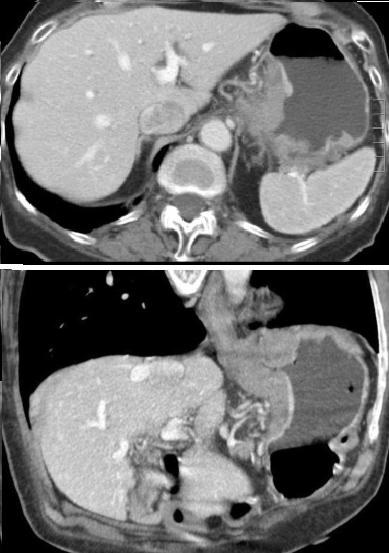

Leiomyome de la face

posterieure de estoma .Image isodense a taillre

marquee , bord reguliere , lisse situe a la face

posteriere de estoma . La paroie de estoma est

normale |

Leiomyome de la petit coubure avec

image ulceree a la surface . Image TDM en coupe

axiale a ingestion baryte . |